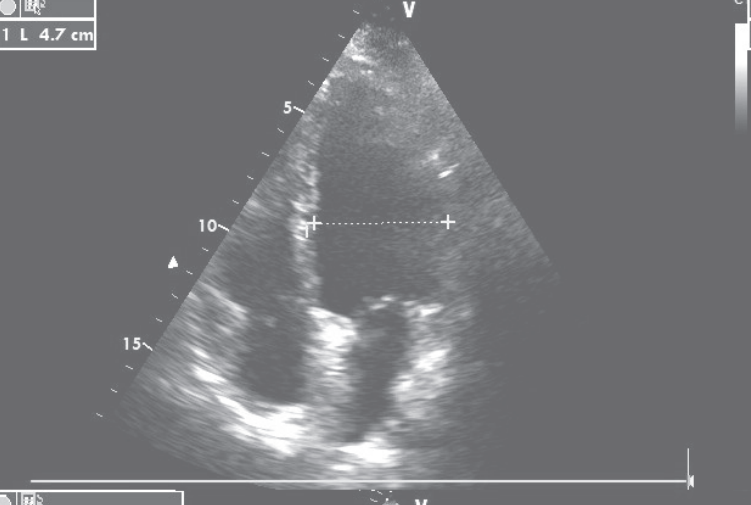

先后予葡萄糖酸钙、乳酸钙(6000 mg/d)、骨化三醇(0.5μg/d)治疗,低钙血症逐渐纠正,1个月后LVEF恢复至30%,NYHA心功能II级。继续补钙治疗,1年后调整每日用药为“乳酸钙3g、α-钙剂2μg、卡维地洛12.5 mg、左甲状腺素150μg”,复查心脏超声,左心室舒张末期内径47 mm,左心室收缩末期内径33mm,LVEF 58%(图5)。

图5 复查心脏超声